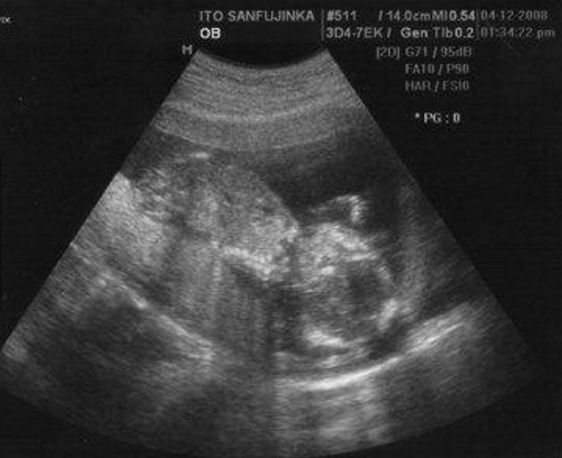

Một cụ bà 91 tuổi tại Trung Quốc bỗng nhiên thấy đau bụng và khó chịu nên đã được gia đình đưa đến bệnh viện kiểm tra. Tại đây mọi người đã sốc nặng khi nghe bác sĩ báo tin là bà đang mang thai mặc dù chồng đã mất cách đây 50 năm. Hóa ra bào thai đó chính là của bà và người chồng đã mất và bà nó cũng đã tồn tại trong người bà 50 năm nay.

Mới đây, câu chuyện một cụ bà người Trung Quốc mang thai ở tuổi 91 đã gây xôn xao dư luận bởi vì ở độ tuổi như cụ bà mà mang thai thì quả thật là chuyện cực hiếm thấy. Được biết, thời gian gần đây bà Đặng thường cảm thấy đau bụng, khó chịu và nôn nao trong người nên đã được các con đưa đi khám. Thế nhưng, cả gia đình bà đã phải thất kinh sợ hãi khi biết tin bà Đặng đang mang thai.

Vì không tin chuyện mẹ mình lại có thể mang thai ở tuổi 91 nên con trai bà Đặng đã đưa bà đến kiểm tra ở một bệnh viện khác. Nhưng kết quả vẫn là bà Đặng đang mang thai. Hơn nữa, tác giả của bào thai đó không ai khác chính là chồng bà, người đã qua đời cách đây 50 năm.

Sợ hãi có điềm chẳng lành mà người cha quá cố báo về, con trai bà Đặng đã cố gắng hỏi mẹ thì được bà cho biết, bà đã mang thai trước khi cụ ông qua đời vài tháng nhưng thai nhi nằm bên ngoài tử cung và cần phải loại bỏ.

Bào thai đã nằm trong bụng bà hơn 50 năm kể từ ngày chồng bà qua đời.

Lúc đó, bà không có đủ tiền để loại bỏ cái thai đó nhưng cũng vì xót xa cho đứa con yểu mệnh nên bà đã bỏ về nhà và giữ lại cái thai như kỉ niệm cuối cùng với người chồng đã mất. Chuyện bà Đặng mang thai đã khiến nhiều người xót xa xúc động. Tuy cụ ông đã mất mấy chục năm nhưng cụ bà vẫn một lòng một dạ nhớ về ông.